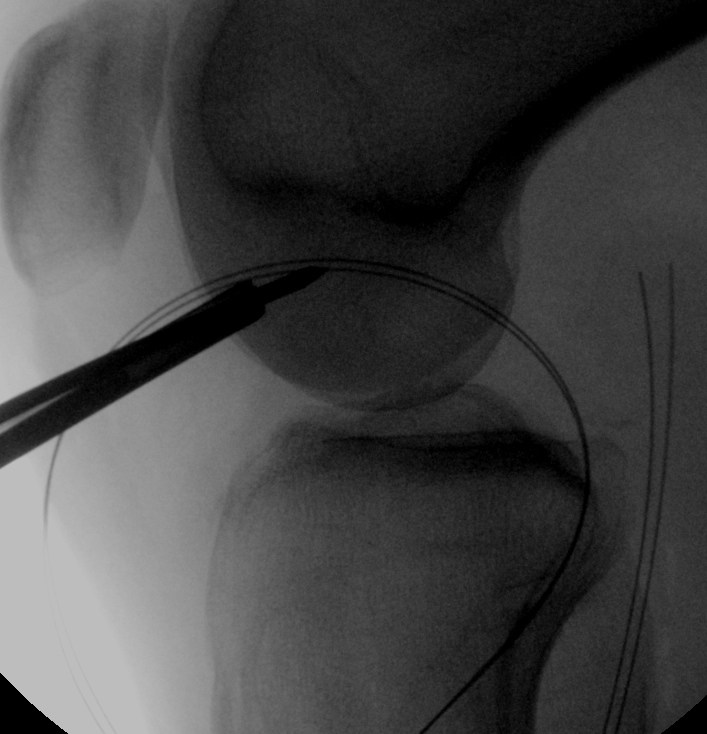

Femoral tunnel

- isometric point

- line parallel to Blumensaat's

- largest part of femoral condyle

- 40% from anterior aspect

- ensure 1 cm from articular cartilage

- pass wire, drill outside in

- pass loop wire